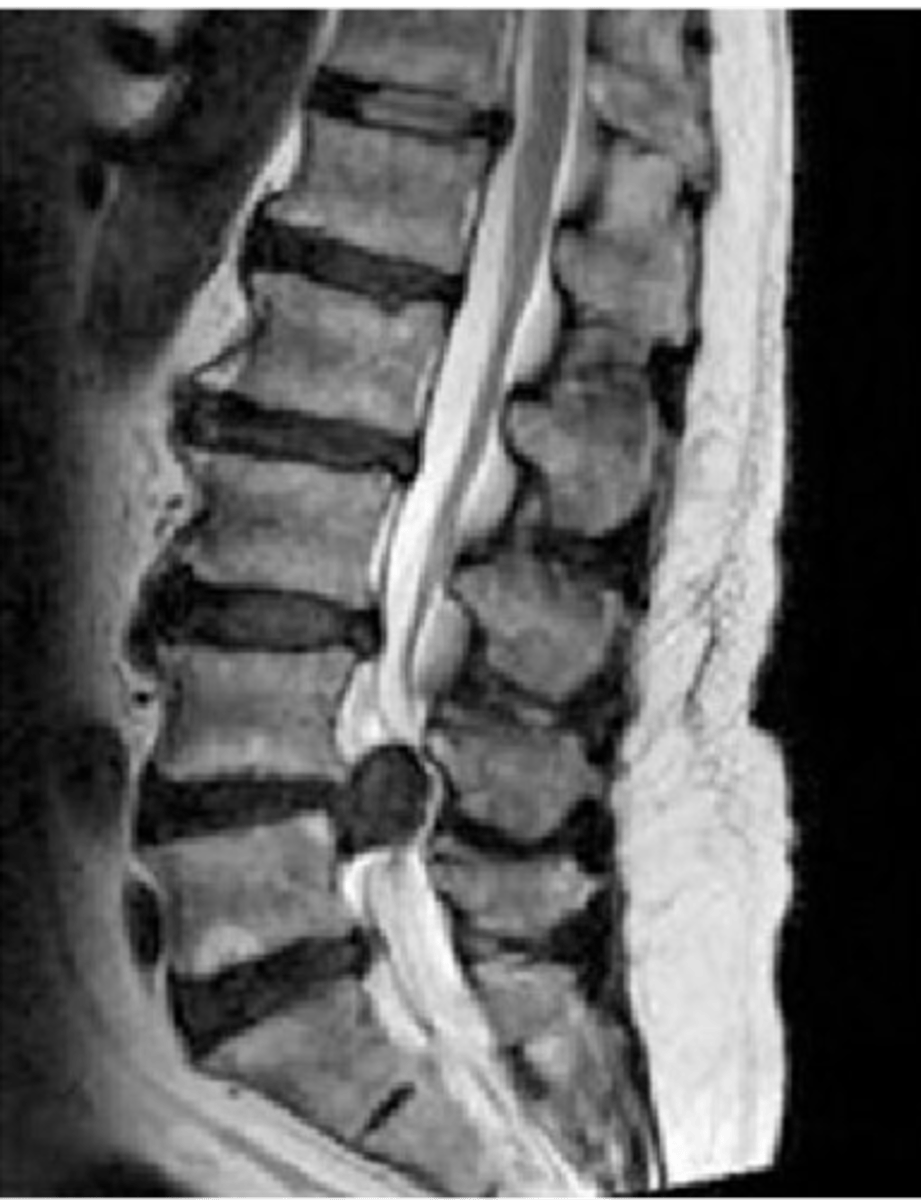

CT myelography can be used to evaluate the ____ and _____

spinal cord and canal

CT myelography is a good alternative to MRI to identify

spinal stenosis, disc herniation, spondylosis, arthritis

herniated disc disease

spondylosis

arthritic degeneration of the spine

spondylosis is generally accompanied by ____ formation and disc ______

osteophyte formation and disc thinning/collapse

_____ is a common cause of low back pain but can occur anywhere

spondylolisthesis

forward slipping of one vertebra over another (caused by vertebral fracture at the pars interarticularis)

spinal stenosis

Narrowing of the spinal canal that causes pressure on the spinal cord (nerves)

spinal stenosis etiology

osteophytes, disc herniation, tumors, trauma